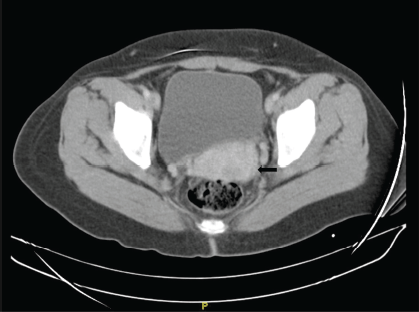

She is subsequently referred to the National Institute of Neoplastic Diseases (22.08.2016) and is seen in the gynecologic oncology service, where she is evaluated. Patient ECOG 1, no peripheral adenopathies. External genitalia preserved, at speculoscopy 2 cm tumour is observed dependent on the posterior lip of the cervix. Digitorectal examination: Parametrium free. Complementary studies with tomography of the thorax, abdomen and pelvis (30.08.2016): Uterus with regular borders and contours. Prominent cervix of 5.3 cm of greater diameter, in the posterior lip, there is a hypocaptive area of contrast in an extension of 2 cm, which could correspond to a lesion. No adenopathies are observed in the iliac chains. No free liquid is observed in the cavity (Figure 1). MRI of the pelvis with contrast (2.9.2016): thickening at the level of the cervix of 2 × 2 cm that shows restriction to diffusion and enhances with the contrast substance. No parametrial involvement (Figure 2).

Figure 1. Chest, abdomen and pelvis tomography with contrast. Transverse section. Prominent uterine cervix, in the posterior lip there is a 2 × 2 cm area of contrast uptake (→).